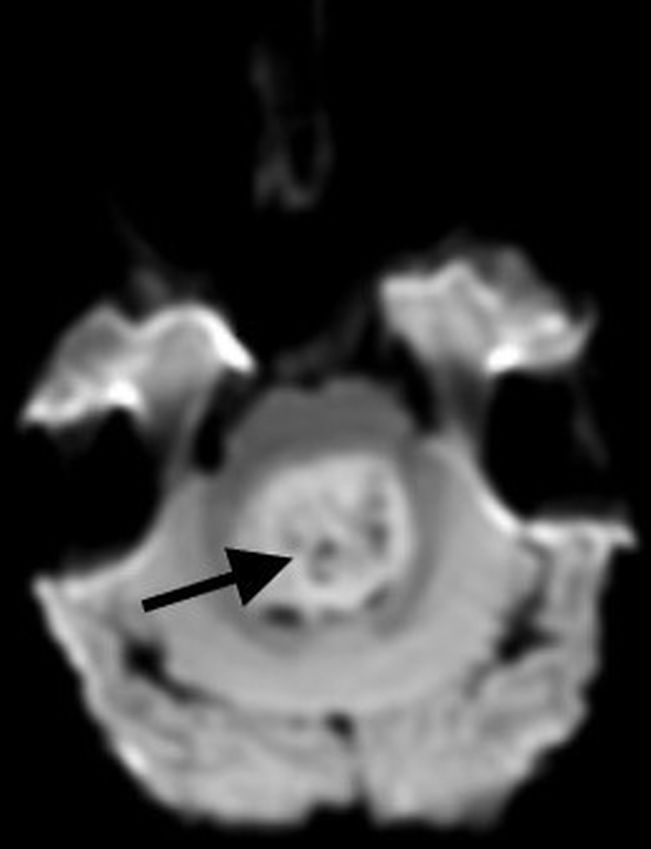

Posterior fossa pilocytic astrocytomas most often arise within the cerebellar hemispheres and are therefore lateral in location. Less commonly, they may be midline, arising from the cerebellar vermis. The classic imaging appearance is a large cystic mass with a peripheral solid nodule. More heterogeneous presentations, including a multicystic mass, predominantly solid mass with central cystic changes, or partially hemorrhagic mass, are less common [7, 17].

On MRI, the cystic component of the tumor is often similar to CSF signal intensity on T1 and T2 sequences, with the T2-FLAIR signal being more variable, based upon internal proteinaceous content. Solid portions of the mass avidly enhance, and there may also be enhancement along the margins of the cyst wall. A helpful distinguishing feature of a pilocytic astrocytoma, compared to other posterior fossa tumors, is the lack of diffusion restriction within the solid components of the tumor [18, 19] (Fig. 2).